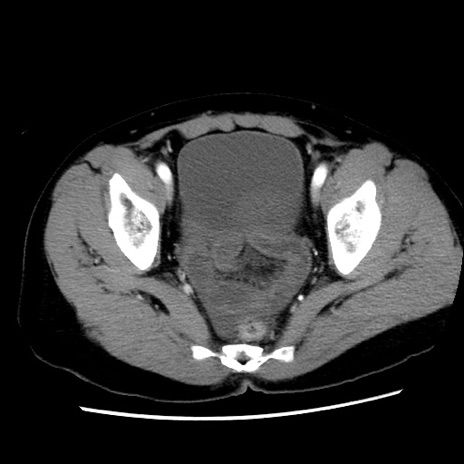

症例10(横断像)

【症例】 50歳代女性

【主訴】 腹痛

【現病歴】前日生レバーを食べた。今朝に排便あり。 昼前に突然発症の腹痛を生じ、当院救急外来を受診した。

【既往歴】 子宮筋腫にてで子宮全摘後

【身体所見】 意識清明、腹部:平坦、軟、下腹部やや左を中心に圧痛・反跳痛あり、筋性防御あり

【データ】WBC 7800、CRP 0.07